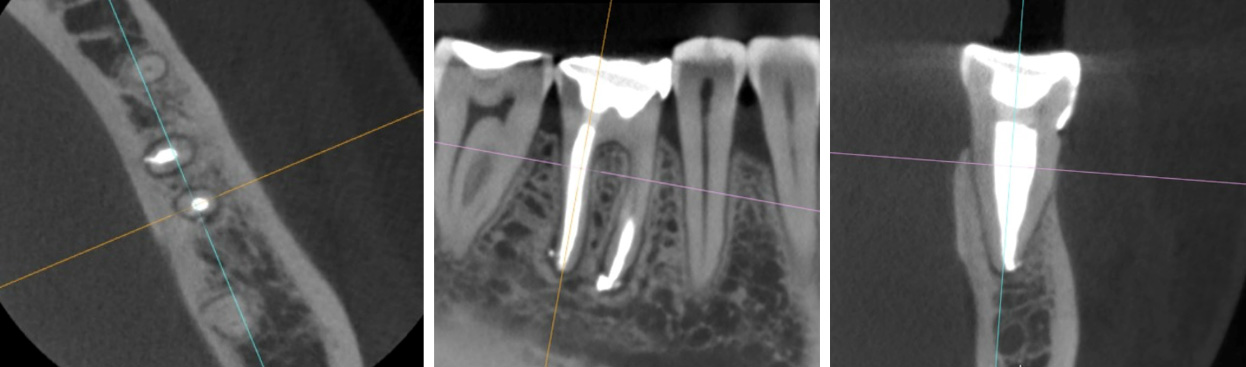

A 6-month tomographic follow-up showed complete reduction of the apical periodontitis.

6 months PO CBCT